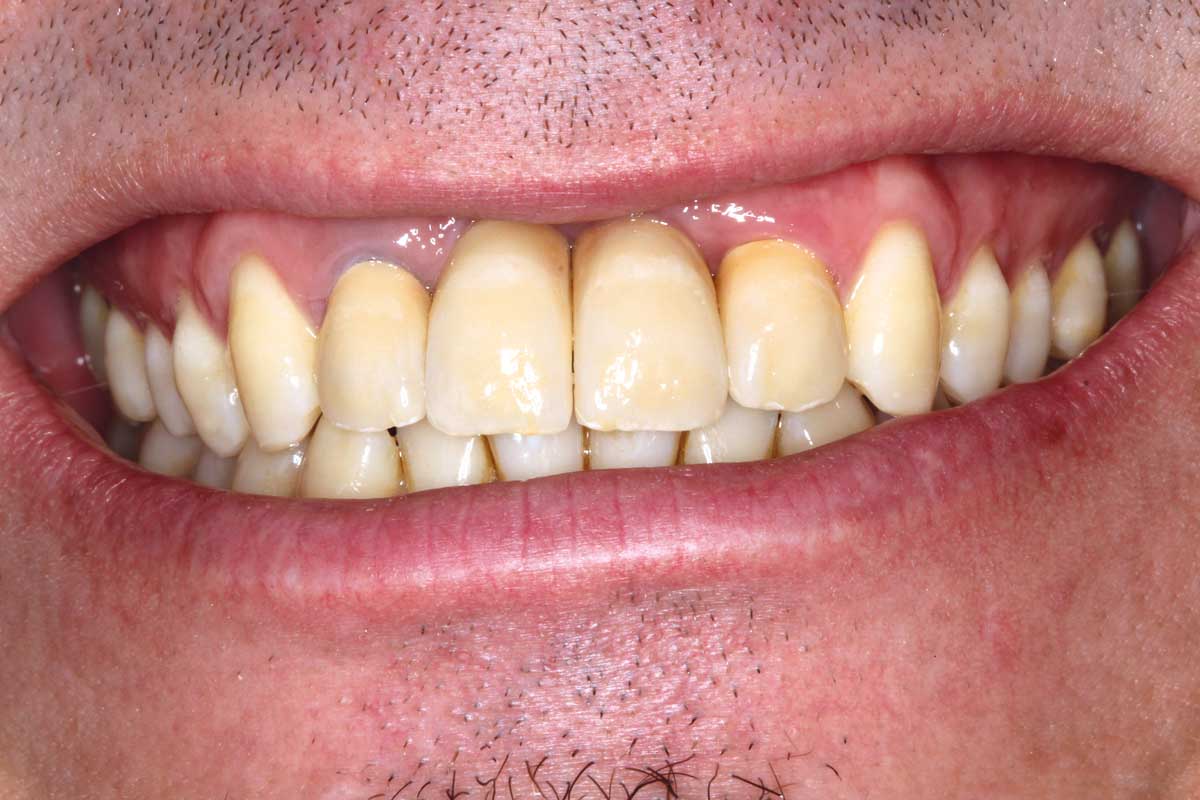

01/26 - Bone defect in area 11-21 due to two lost implants (periimplantitis) after 15 years of function

Ridge augmentation in the maxilla with maxgraft® bonebuilder in the aesthetic zone - Dr. M. Kristensen